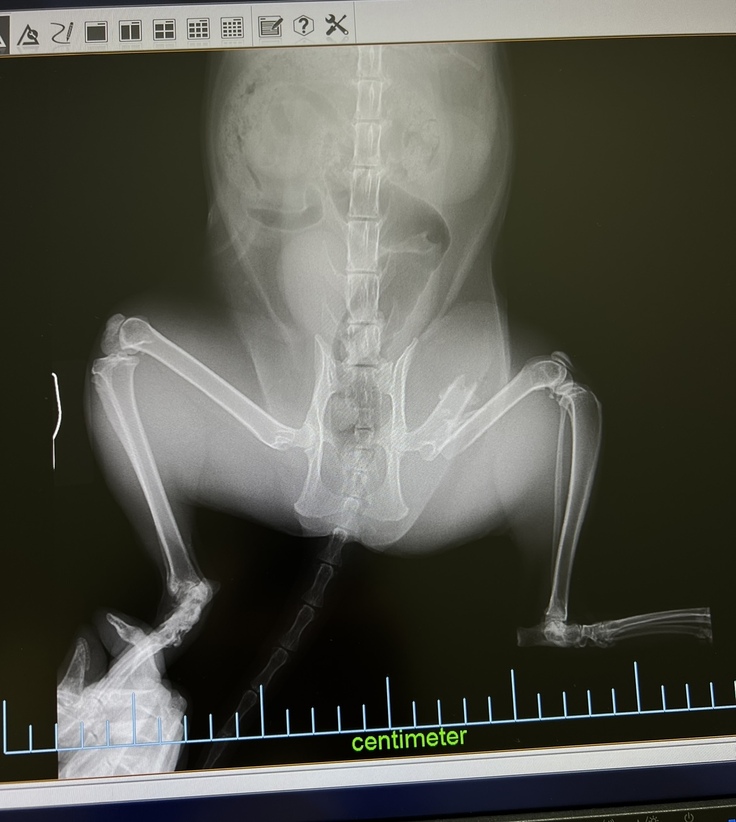

すぐに動物病院に連れて行き、レントゲンをとった結果、左後脚が斜骨折。

その拍子で皮膚から骨が突き出した形跡があり、体も打撲している為、

交通事故による骨折だろうと診断されました。

手術前

幸いにも、内臓や骨盤の異常は見られませんでしたが、

骨が突き抜けた拍子に感染しているかもしれない。

感染の度合いによっては将来切断の可能性もあるとの事でした。

まずは必要検査などを行い、そのまま入院し翌日手術を行う事にしました。

骨が斜に長く折れているのでプレートで固定をすることができない為、

ピンを入れる手術を行いました。